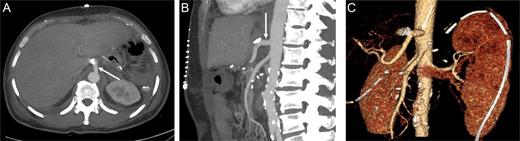

A 60-year-old male, with irrelevant medical history (no chronic disease or treatment), and complaining of recurrent abdominal pain, was referred for abdominal computed tomography (CT). Due to a suspicion of a mass in the pancreatic body (Fig. 1), the patient was referred to our hospital for re-evaluation and treatment. Physical examination was not remarkable, besides epigastric pain during deep palpation. All blood tests were within normal ranges. In re-evaluation of a previous CT, performed in a different hospital, our Radiological Department reported: ‘a malign appearing mass in the pancreatic corpus with extension to the pancreatic neck, with no invasion of the Superior Mesenteric Artery (SMA) and Superior Mesenteric Vein (SMV)’. Laparotomy was performed. Intraoperatively, a mass of ∼6–8 cm was discovered, located from the neck to the corpus of the pancreas. During exploration, the leading surgeon noticed that vascular structures, both the superior anterior pancreaticoduodenal artery (SAPDA) and the inferior anterior pancreaticoduodenal artery (IAPDA), which are collaterals between the gastroduodenal artery (GDA) and the SMA, were enlarged and tortuous. After the Kocher maneuver, all resections (jejunal, postpyloric gastric, common bile duct) were performed. Immediately after the GDA was clamped and cut, an ischemic appearance was seen on the liver and stomach. At this point, it came to mind that there was a total celiac trunk occlusion or possible MALS. To prevent ischemic hepatic injury, immediate re-anastomosis of the cut GDA was performed. After re-anastomosis was completed, a rapid change in the color of the liver and stomach was observed. And after re-anastomosis of the GDA, digital palpation and Doppler ultrasonography revealed that circulation of the common hepatic artery, splenic artery and left gastric artery was restored, and all these vascular circulations were from the SMA via the GDA.

Preoperative computer tomography, mass (arrow) located in corpus of the pancreas.